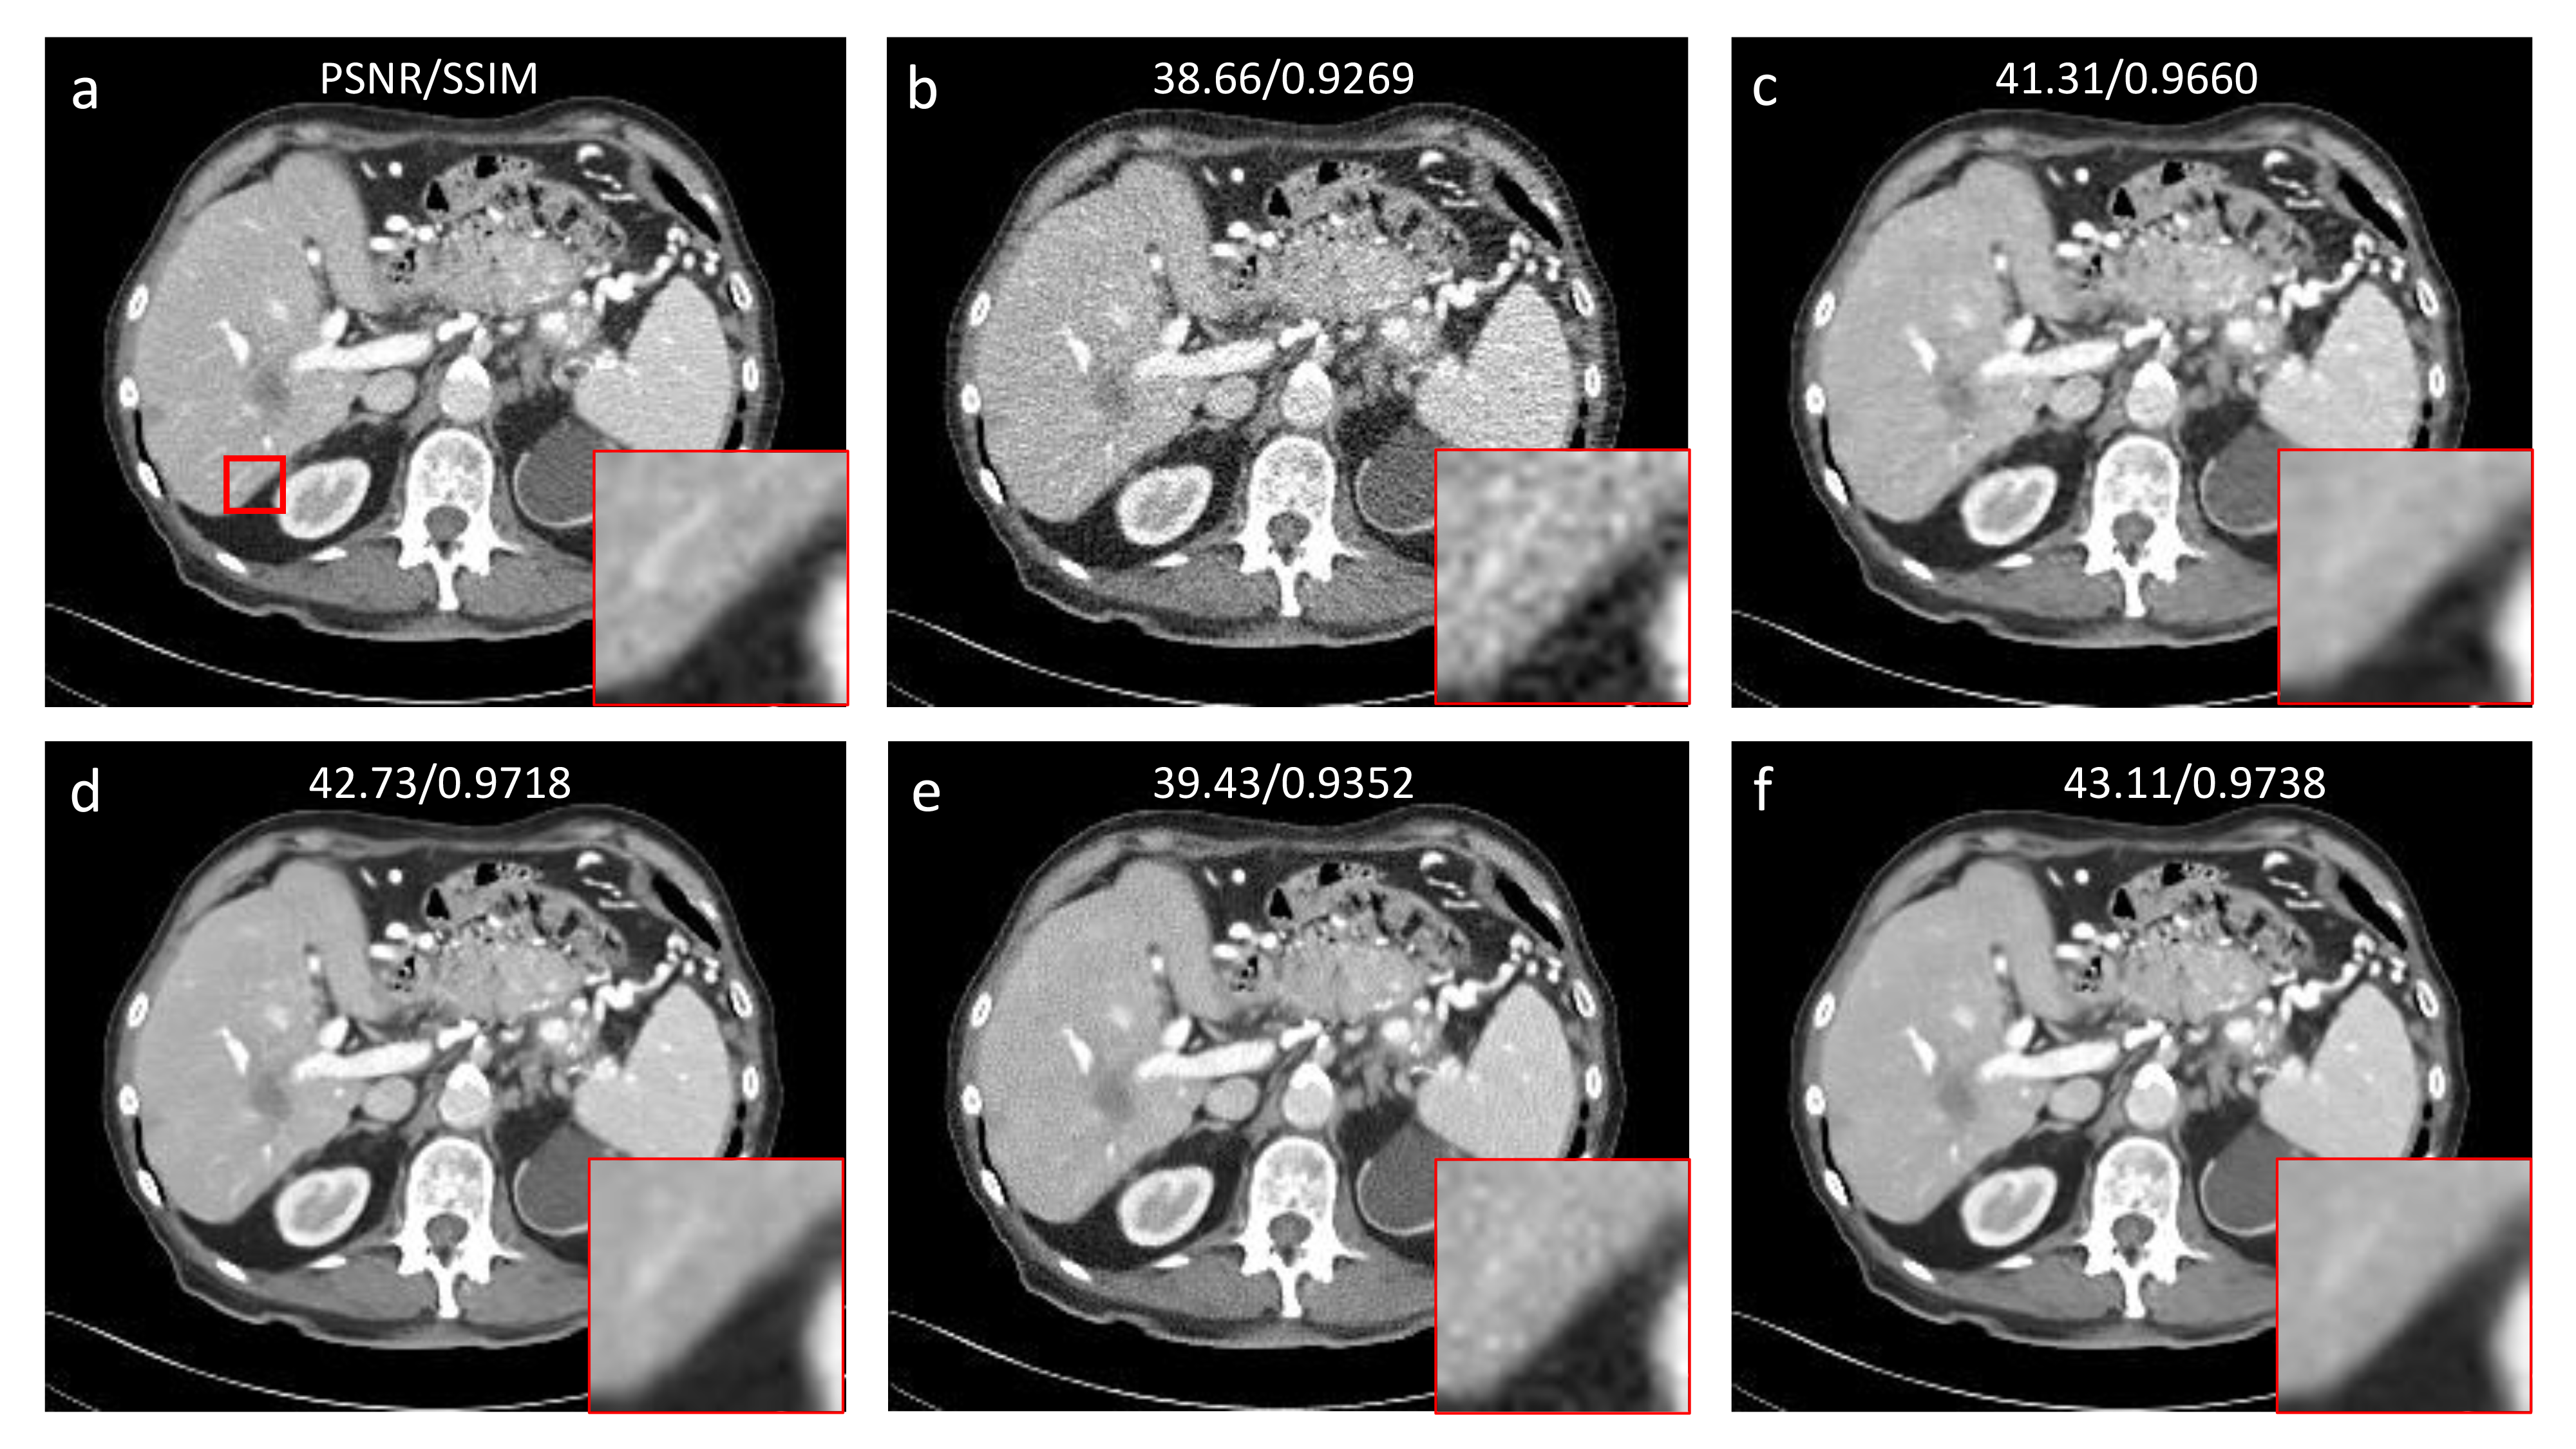

Figure 2: The results obtained using different methods. (a) NDCT, (b) LDCT, (c) U-Net, (d) DDPM, (e) DPM-Solver 15 NFE, and (f) DPM-Solver 50 NFE. The display window is consistently set to [-160, 240] HU.

Fig. 2 shows the results obtained using different methods. It can be seen that U-Net ronneberger2015u failed to eliminate image noise completely. With DDPM, image noise was effectively removed while the structures were well kept. With only 15 NFE, the DPM-Solver could not denoise LDCT images well. Because of a too few number of sampling steps, residual noise and newly generated noise are evident in the resultant images sampled with DPM-Solver 15 NFE. Remarkably, after NFE was increased to 50, the DPM-solver delivered a competitive performance relative to that of DDPM. It can be seen that in the magnified region of interest (ROI), DPM-Solver 50 NFE well maintained the vasculature, which was blurred by U-Net. Quantitatively, DPM-Solver 50 NFE outperformed DDPM. Fig. 3 shows the absolute error maps of the abdominal results shown in Fig. 2 in reference to the NDCT image. It further demonstrates the efficient and effective sampling performance of the DPM-Solver, whose error map is the least noisy.